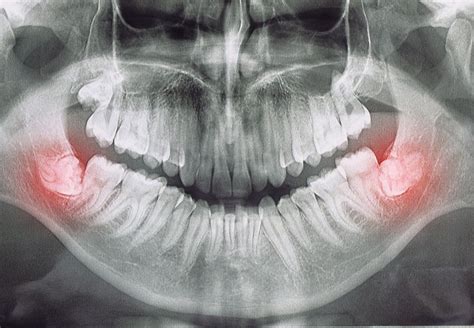

Después del tratamiento de ortodoncia, es habitual que el ortodoncista recomiende la extracción de las muelas del juicio, especialmente las inferiores. Sin embargo, en muchas ocasiones, el cirujano maxilofacial advierte que puede haber problemas si se extraen, ya que están muy cerca del "nervio mandibular".

Después de solicitar una tomografía (TAC) que confirma su sospecha, va a desaconsejar su extracción. Sin embargo, según como estén situadas estos terceros molares, es posible que con el tiempo aparezcan problemas (bien porque se apiñan los dientes inferiores, o que alteren la encía o el diente adyacente generando dolor o inflamación).

La extracción en estos casos tiene un riesgo de lesionar el nervio creando una sensación de parestesia (acolchamiento) en casi uno de cada diez casos, aunque en la mayoría de ellos será reversible.